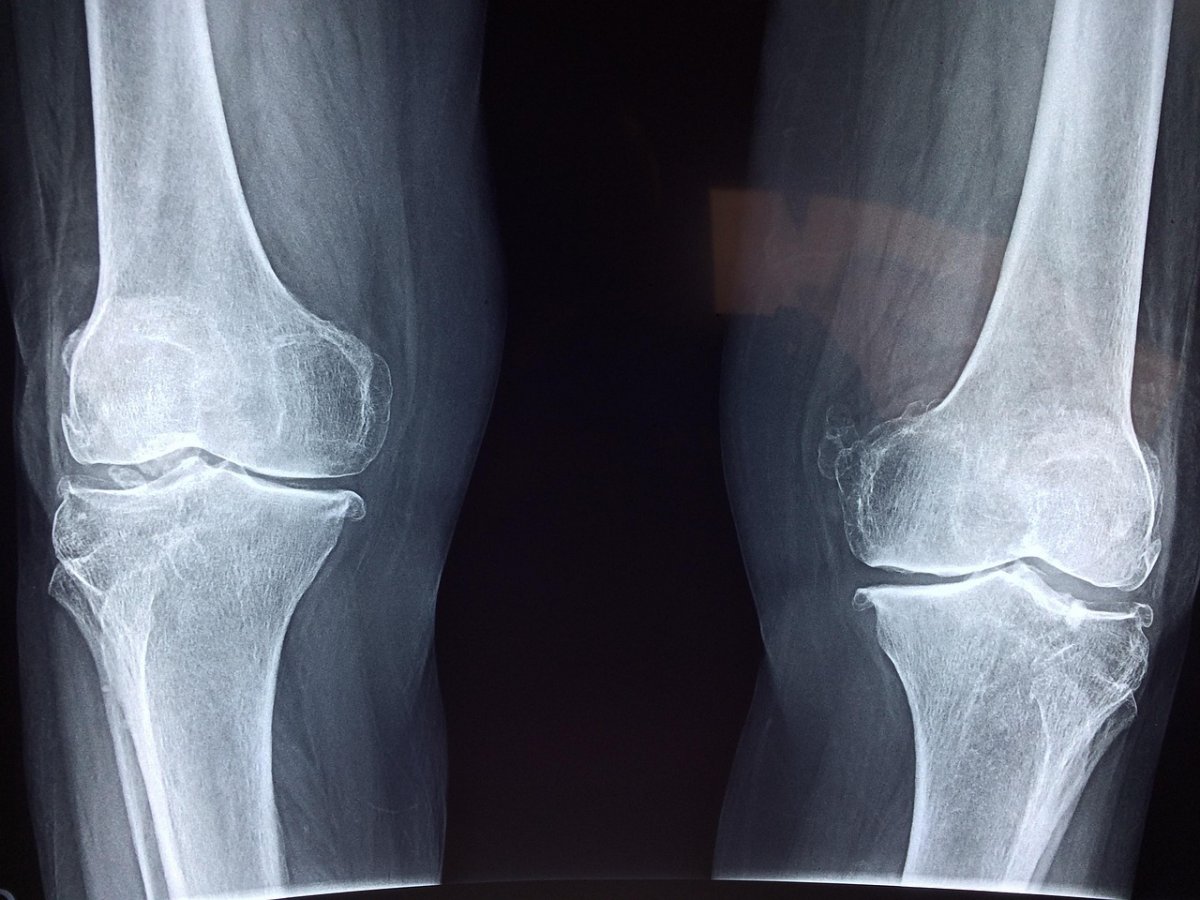

“В настоящее время мы лежим в больнице, перенесли сложную операцию. Реабилитация от одного года до двух-трех лет. Куда мне обратится? Почему ничего не загорожено? Кто будет отвечать за эти раскопки, из-за которых мой ребенок сейчас лежит с тяжелейшими травмами в больнице?” – спрашивает мама мальчика Гульшат в одном из семейских пабликов.